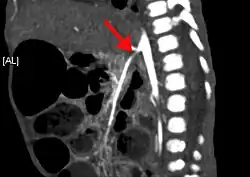

| CT angiogram demonstrating stenosis of the superior mesenteric artery. | |

Abdominal angina is diagnosed by identifying stenosis with imaging.[10] Since the symptoms of abdominal angina overlap with various other disorders, other causes of symptoms are ruled out as a part of the diagnostic process. Gastric ulcers, abdominal aortic aneurysms, and gastrointestinal cancers can have similar symptoms and can be ruled out by esophagogastroduodenoscopy, CT scans, or MR angiogram. Other differential diagnoses include GERD, dietary or food sensitivities, constipation, pancreatitis, abdominal abscess, appendicitis, irritable bowel syndrome, gastroenteritis, hepatitis, and inflammation of the gastrointestinal system.[11] Duplex ultrasound, MR angiography, angiography, and computed tomography angiography can be used to help confirm the diagnosis of abdominal angina.[3] Duplex ultrasound may be used to screen for abdominal angina but is not ideal for visualizing stenosis. Angiography, MR angiography, or CT angiography can be used to further visualize the celiac and mesenteric arteries.[12]